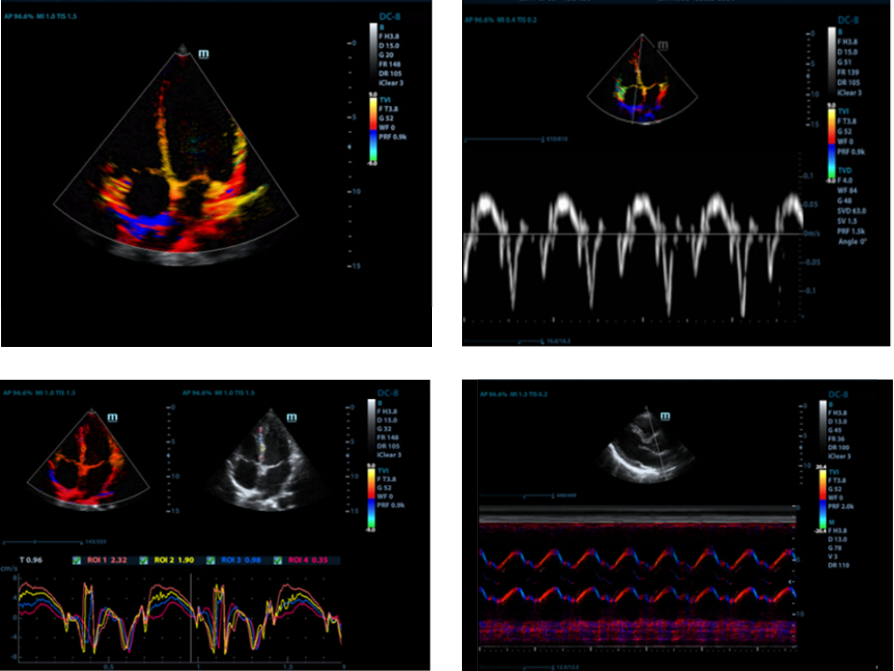

TDI

Tissue Doppler Imaging allows you to quantitatively evaluate local myocardial movement and function, providing complete TDI modes for faster and direct diagnoses.

Free Xros CM?

Accurately evaluate myocardial motion at different phases, and simultaneously determine myocardial synchronisation. The high frame-rate provides accurate results.